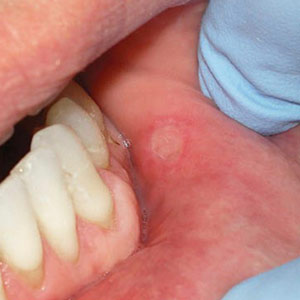

These small sores are called aphthous ulcers or more commonly “canker sores.” They are breaks in the skin or mucosa, the inner lining of the mouth, and occur most often on the inside cheeks, lips, tongue and occasionally on the soft palate at the back of the throat. They usually appear round with a yellow-gray center and an intensely red outer ring or "halo."

Canker sores often appear during periods of high stress or because of minor trauma, and usually last for a week or two. They often have a tingling pain that can be aggravated when you eat and drink acidic or spicy foods and beverages. About 20 to 25% of people have a form known as recurrent aphthous stomatitis (mouth inflammation) that occurs regularly with multiple sores and heightened pain.

It's possible to manage the discomfort of minor, occasional bouts with a number of over-the-counter products that cover the sore to protect it and boost healing, with some providing a numbing agent for temporary pain relief. For more serious outbreaks we can also prescribe topical steroids in gels or rinses, injections or other medications.

While canker sores don't represent a health danger, there are instances where you should take outbreaks more seriously: if a sore hasn't healed after two weeks; if you've noticed an increase in pain, frequency or duration of outbreaks; or if you're never without a sore. In these cases we may need to biopsy some of the tissue (and possibly run some blood tests) to ensure they're not pre-cancerous or cancerous.